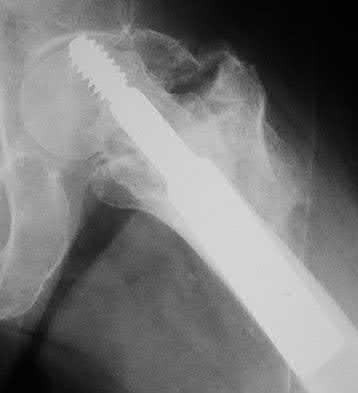

3. # Which of the following is not an appropriate implant for treatment of the fracture seen in Figure A?

1. Cephalomedullary nail

2. External fixation

3. Proximal femoral locking plate

4. 95 degree blade plate

5. Sliding hip screw Corrent answer: 5

The image shows a reverse obliquity intertrochanteric hip fracture.

According to the referenced article by Haidukewych et al, unstable peritrochanteric hip fractures have a worse outcome (failed in 9/16 cases) if treated with a sliding hip screw. Two additional factors that were found to have a strong correlation with postoperative failure (nonunion, loss of reduction) were poor reduction and poor implant placement. In this study, fixed angle devices were superior. Intramedullary fixation has the added advantage of a shorter lever arm and less potential for fracture collapse and limb shortening.

The IMN also acts as a medial buttress.

According to Sanders et al, the dynamic condylar screw (DCS) can also be used in subtrochanteric models, but should not be used if extensive comminution is seen, as they reported a high failure rate with DCS in these fractures if highly comminuted. They report a 77% overall union rate with this device.